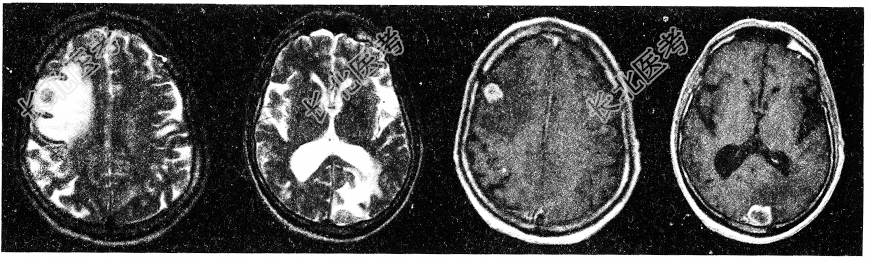

- 单项选择题男性患者,77岁。胃癌术后2年, 头痛1月,请结合影像图像选择最可能的诊断为

C、胃癌脑转移